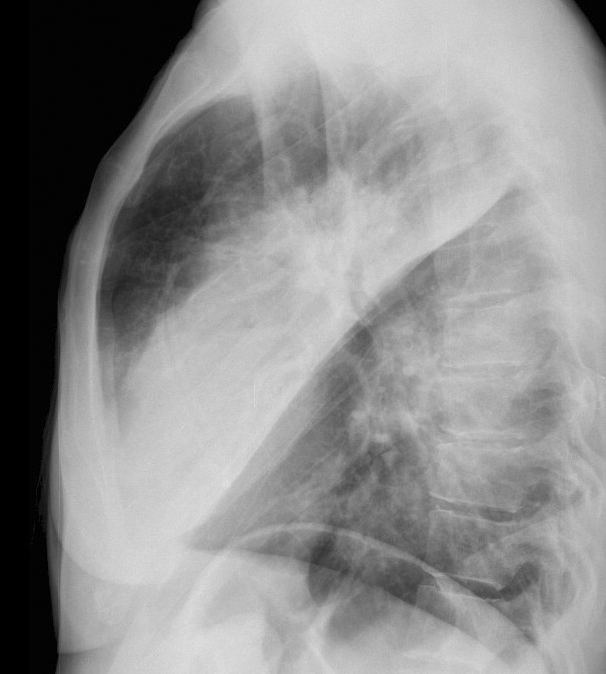

Gallery Pneumonia Case 3 RM & UL pneum Lat

Case 3 RM & UL pneum Lat